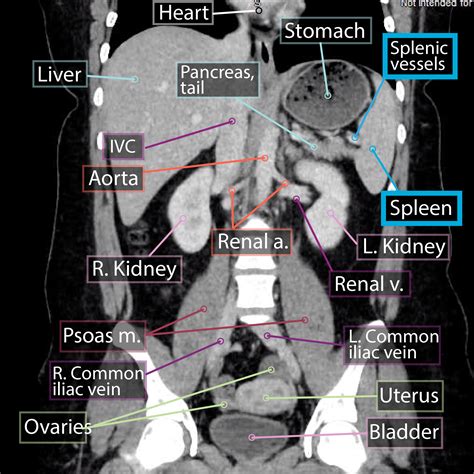

The spleen and pancreas are both located in the upper left quadrant of the abdomen, but they have different anatomical structures and positions. The spleen is a fist-sized organ situated just below the ribcage on the left side, while the pancreas is a long, flat gland that stretches horizontally across the back of the abdomen.

Location Upper left quadrant of the abdomen, below the ribcage Horizontally across the back of the abdomen, behind the stomach

• spleen and pancreas anatomy

• spleen and pancreas location